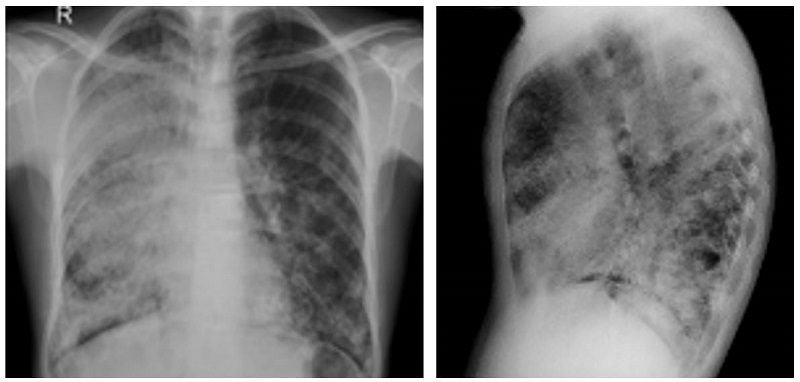

Los hallazgos imagenológicos son sugestivos, pero no son diagnósticos por sí solos: en la radiografía de tórax es característico encontrar opacidades alveolares bilaterales de distribución perihiliar sin broncograma aéreo o “patrón en alas de murciélago”; por otro lado, en la tomografía computarizada (TAC) se espera encontrar el signo del “empedrado” que consiste en un engrosamiento interlobulillar asociado a opacidades difusas en vidrio esmerilado 9,11.

Al ingreso se solicita hemograma con leucocitos: 6300 x 103 mm3, #neutrófilos: 4020, #linfocitos: 1600, hemoglobina: 17,9 g/dl, hematocrito: 53,2 %, plaquetas: 315.000 mm3, radiografía de tórax con evidencia de zonas en vidrio esmerilado generalizadas con predominio en hemitórax derecho (figura 1) por lo cual se solicita tac que evidencia múltiples áreas parcheadas de distribución generalizada de mayor compromiso apical derecho en relación con áreas de vidrio esmerilado asociado a engrosamiento del intersticio interlobulillar que genera patrón en “empedrado” (figura 2).